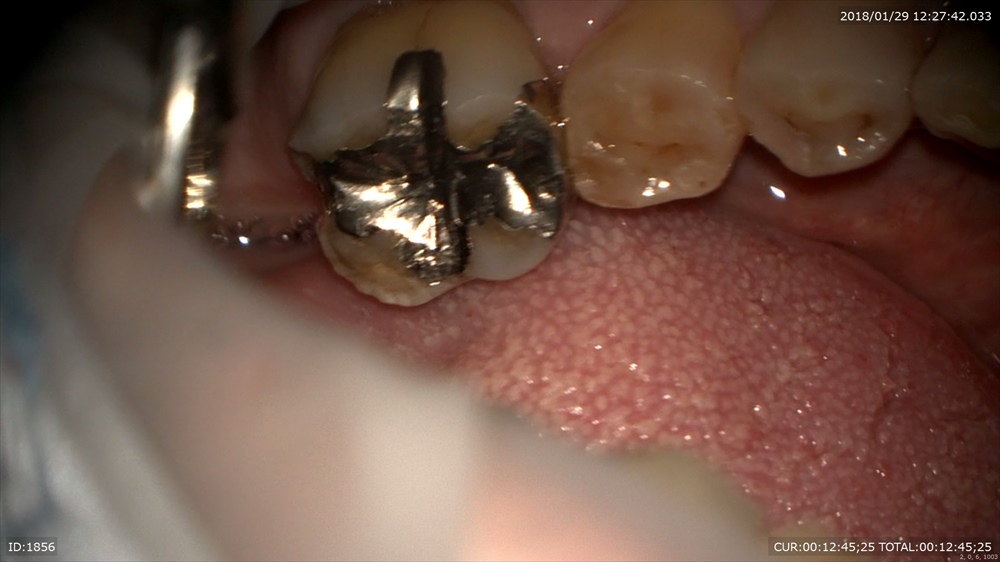

次はむし歯 銀歯の後ろが欠けていました。

外すと 銀歯むし歯